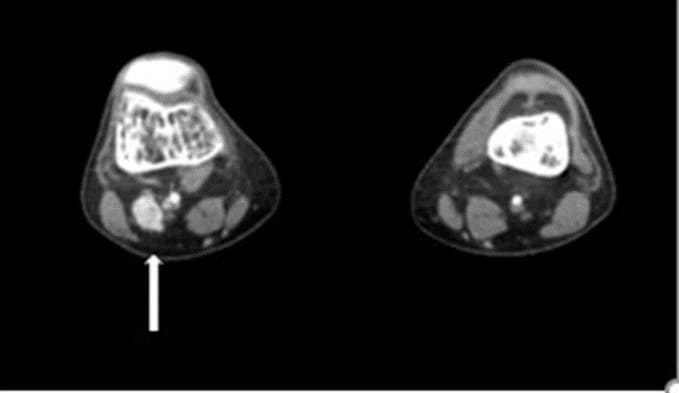

A 28-year-old otherwise healthy male, developed skeletal, muscular and joints pain 5 years’ prior to his arrival to our institution. The patient had no history of smoking, ethanol intake, antiseizure medication, antacid abuse, steroid use, bisphosphonates or antidiabetic medications. Due to severe low back pain, the patient was diagnosed with L5-S1 bilateral spondylolisthesis and treated with bilateral pedicle screw hook fixation (Figure 1). In spite of the treatment, the patient continued to deteriorate, he became bedridden due to severe pain and fatigue, until his referral to our institution. Upon his arrival, the radiological survey revealed a convex deformity of both his hips with subcapital fracture of the right femur (Figure 1), multiple rib and vertebrae fractures (Figure 2A), fracture of the left scapula (Figure 2B), fracture of the sternum (Figure 2C), severe pectus carinatum with thoracic and sacral kyphosis (Figure 2D). A DXA study showed severe osteoporosis (T score <-2.5) [10]. Biochemical investigations revealed a low serum phosphorus level (1.1 mg/dL) and an elevated alkaline phosphatase level (287 u/l). Serum creatinine, calcium, and albumin were found to be normal. Serum 1,25-dihydroxyvitamin D level was low (10.1pg/ml). This data led to the suspicion of TIO. As a result, we evaluated the levels of FGF23 in the blood. The plasma FGF23 levels were collected from the right and left median cubital veins and from the femoral veins and showed levels of 1802 pg/ml, 1816 pg/ml, 2319 pg/ml, and 1806 pg/ml, respectively (normal reference range: 23.2 – 95.4 pg/ml). A 68GA-DOTATATE PET/CT scan demonstrated uptake in a 2.5 cm x 1.6 cm lesion located in the right popliteal fossa. The patient was referred to the orthopedic oncology surgical unit with the diagnosis of a possible phosphaturic mesenchymal tumor. After clinical evaluation of the tumor, MRI and CT studies with contrast injection of the right knee were performed. The studies demonstrated a soft tissue lesion in the right popliteal fossa, 2.3 cm in diameter, located adjacent to the popliteal vessels, the tibial nerve and the common peroneal nerve (Figure 3). Once the dimensions and the borders of the lesion were defined and confirmed, surgical treatment was recommended. A wide resection of the tumor was performed. Histopathological examination disclosed a mesenchymal tumor, composed of spindle cells and osteoclast-like giant cells, with free surgical margins. 14 hours post-surgery, blood samples presented a normal FGF23 level (52.67 pg/ml). One-week post-surgery, the levels of serum phosphorus also returned to normal (Figure 4).

Figure 3: CT with IV contrast injection demonstrating enhancement of a small soft tissue mass in the popliteal fossa of the right knee, located adjacent to the lateral aspect of the popliteal vessels and the tibial nerve and medial to the common peroneal nerve.